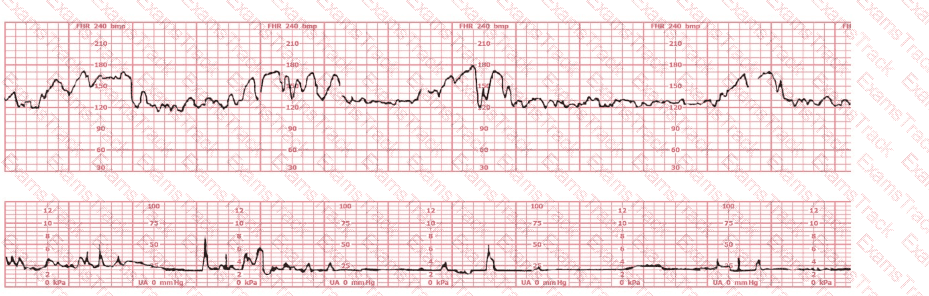

The fetal heart rate tracing shown demonstrates:

A fetal heart rate tracing is abnormal. A change in maternal position and oxygen administration do not correct the pattern. Following birth, a fetal cord blood sample is taken:

These results are best interpreted as:

Fetal respiratory acidosis is most likely to present with which of the following fetal heart rate decelerations?